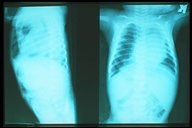

Plain chest X-ray AP (left picture) and lateral ( right picture) showcd soft tissue mass on the right chest cavity with well defined border (soft tissue mass shadow) in a child with hiatal hernia